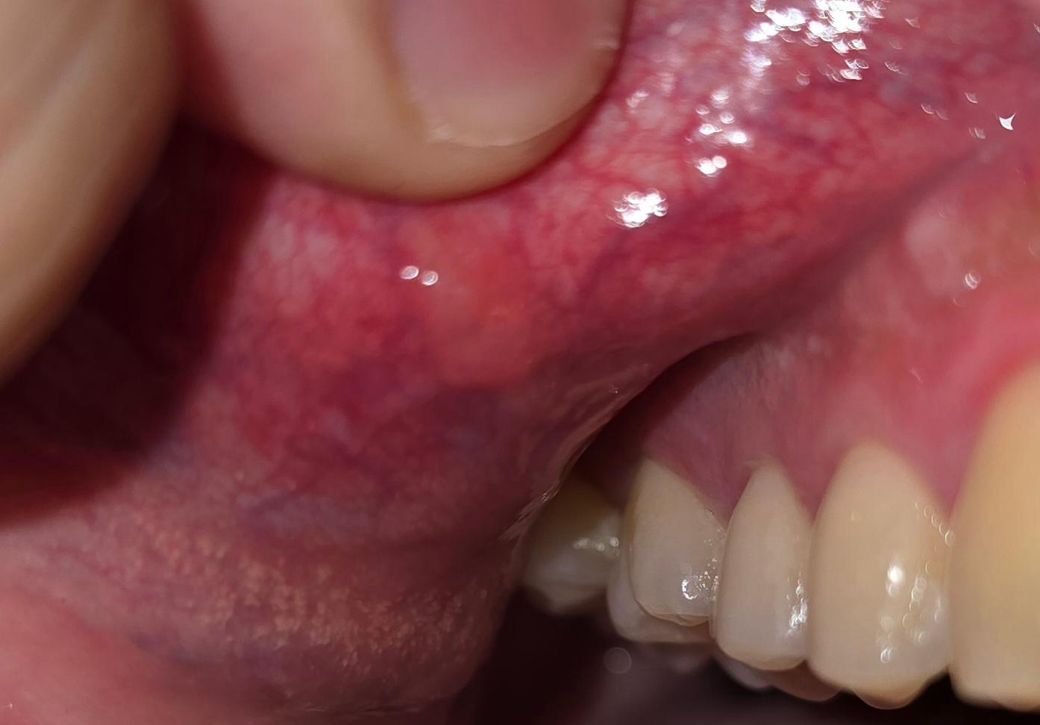

윗 입술을 뒤집어서 깐 사진입니다!

사진으론 어떨지 모르겠으나 길쭉한 모양이고 약간 딱딱한 편이고 통증은 없습니다.. 혹시 위험한 병일수도 있을까요?

사진 기준으로 보이는 병변은 대체로 아래 범주에서 설명될 가능성이 높습니다.

1. 점막섬유종

입술을 자주 깨물거나 반복적인 자극이 있을 때 점막 아래 콜라겐이 뭉쳐 생기는 작은 혹입니다.

모양이 길쭉하거나 약간 단단한 경우가 많고, 통증이 거의 없습니다. 수개월 이상 그대로 있거나 서서히 커지기도 합니다.

이 조합이면 점막섬유종 쪽 가능성이 상대적으로 높습니다. 위험한 병(암 등)으로 진행되는 경우는 매우 드뭅니다. 다만 몇 주~몇 달 지속되거나 크기가 커지는 경우는 확인 필요합니다.